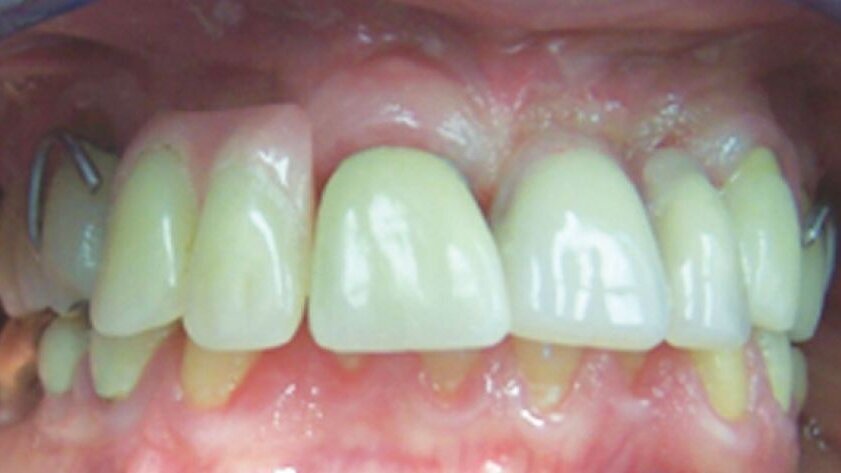

Lorsque le patient s'est présenté à notre clinique, la seule partie de la restauration qui était encore présente dans sa bouche était le pilier de la 13, qui était encore relié à l'un des implants fracturés, et a été enlevé avec un tournevis hexagonal (Fig. 3).